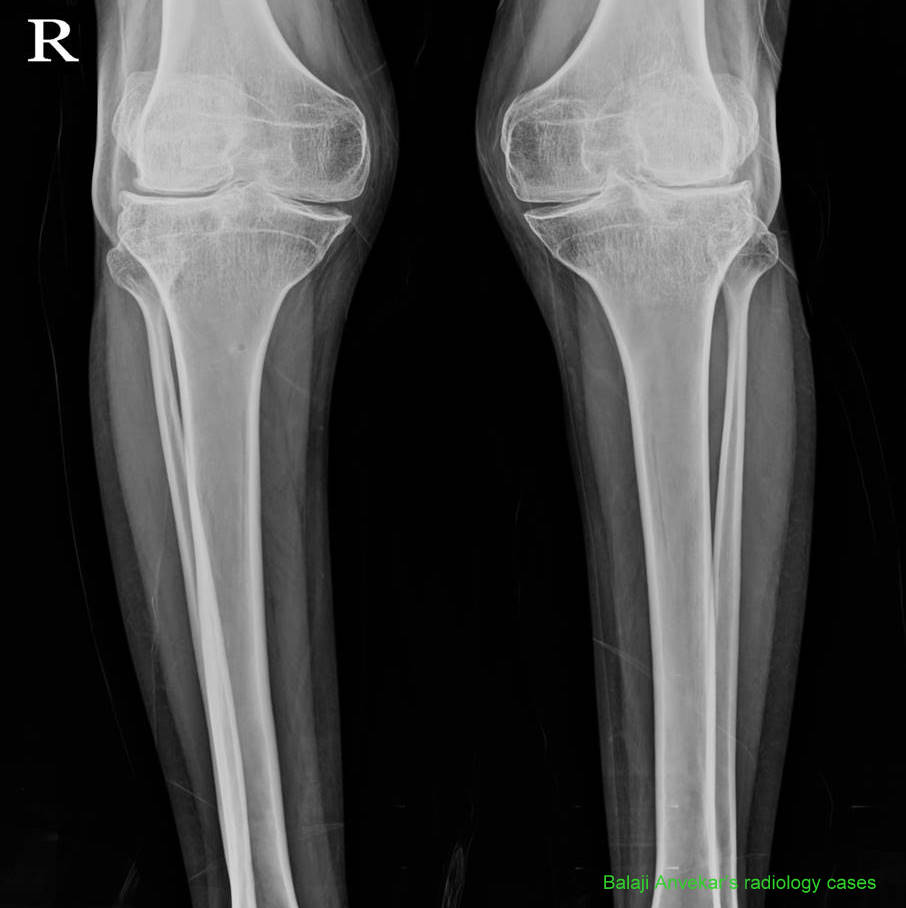

La pseudoacondroplasia, también llamada displasia espondiloepifisaria, es una enfermedad hereditaria que afecta al crecimiento de los huesos y puede provocar enanismo. Causa diversas malformaciones, entre ellas piernas arqueadas, laxitud articular, escoliosis y manos y pies cortos y anchos. Se clasifica dentro del grupo de las osteocondrodisplasias.[1][2]

La expectativa de vida es normal, sin embargo la talla de adulto es baja y oscila entre los 82 y 130 cm. Suele desarrollarse artrosis precoz en diferentes articulaciones, con el consiguiente impacto sobre la calidad de vida.[2]